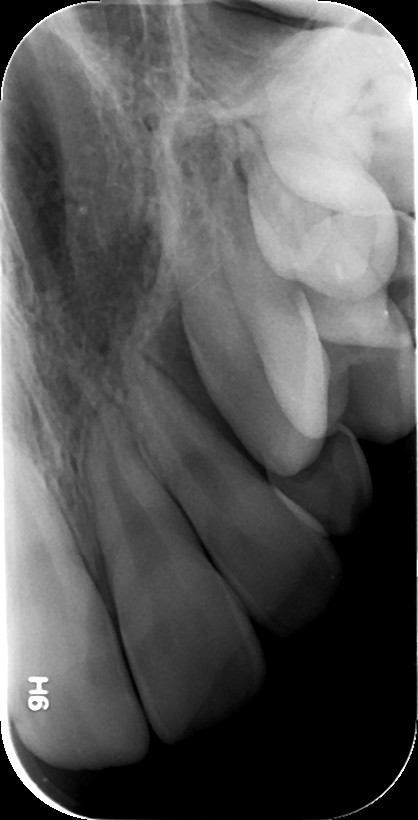

4. ΑΚΤΙΝΟΓΡΑΦΙΑ ΔΗΞΕΩΣ

Πρόκειται για ενδοστοματική ακτινογραφία κατά την οποία το πλακίδιο-φιλμ τοποθετείται οριζόντιο στο επίπεδο των δοντιών του ασθενούς (μασητικό επίπεδο) και συγκρατείται στη θέση του με το κλείσιμο του στόματος. Η πηγή ακτινοβολίας τοποθετείται κάθετα στο πλακίδιο, είτε άνωθεν του ασθενούς εάν θέλουμε να απεικονίσουμε την άνω γνάθο και υπερώα (ουρανίσκο), είτε κάτωθεν του ασθενούς εάν θέλουμε να απεικονίσουμε την κάτω γνάθο και το έδαφος του στόματος.

Με την εξέταση αυτή μπορούν να απεικονιστούν:

• το έδαφος του στόματος για την ύπαρξη λίθων στον εκφορητικό πόρο των σιελογόνων αδένων (Υπογνάθιος και Υπογλώσσιος)

• η εντόπιση, κλίση και φορά έγκλεισης (παρειο-γλωσσική ή παρειο-υπερώϊα) έγκλειστων και υπεράριθμων δοντιών, καθώς και η θέση τους σε σχέση με άλλα δόντια

• η παρειογλωσσική/παρειοϋπερώϊα ανάπτυξη παθολογικών αλλοιώσεων των γνάθων

• κατάγματα των γνάθων και των δοντιών

• υπερωο-γναθοσχιστίες.

Η λήψη της είναι γρήγορη (διαρκεί λίγα δευτερόλεπτα) και ανώδυνη.